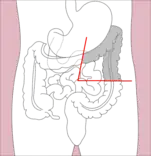

- Right hemicolectomy and left hemicolectomy refer to the resection of the ascending colon (right) and the descending colon (left), respectively. When part of the transverse colon is also resected, it may be referred to as an extended hemicolectomy.[5]

Left hemicolectomy Extended left hemicolectomy

Extended left hemicolectomy - Transverse colectomy is also possible, though uncommon.